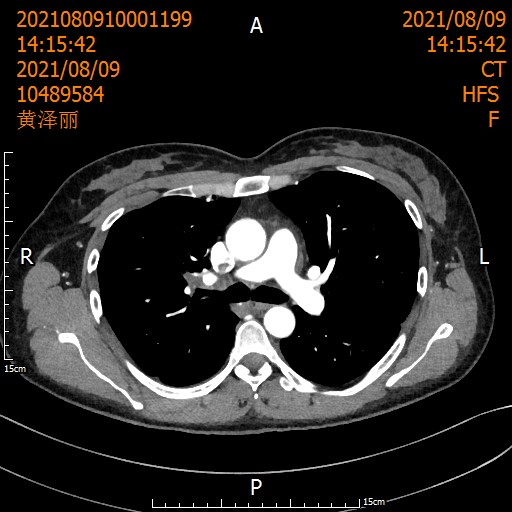

遵循《国际专家共识》,刘浩团队启动了术前2周期化疗联合3周期"卡瑞利珠单抗+紫杉醇/卡铂"治疗。

治疗后患者影像

经过术前新辅助治疗后,医生又为她精心策划了根治性手术,团队紧密配合,顺利完成。